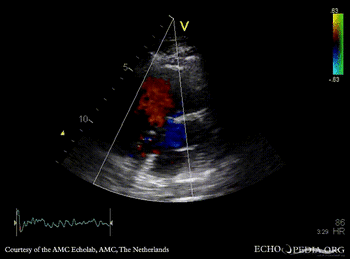

| PSAX: ASD type I | Subcostal view: ASD type I |